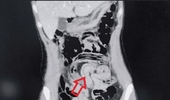

더지엠뉴스 이남희 기자 | 극심한 복통으로 병원을 찾은 20대 여성이 맹장 수술을 받은 직후 구토 과정에서 살아 있는 회충을 입으로 토해낸 사례가 국제 학술지에 보고됐다. 장 속에 숨어 있던 기생충이 충수 안쪽까지 파고들어 염증을 일으킨 뒤 위 방향으로 역행한 것으로 추정되면서, 위생 관리와 정기적인 구충의 필요성이 다시 떠오르고 있다. 24일 국제 의학 저널 큐레우스에 따르면, 필리핀 국적의 29세 여성 A씨는 심한 배 통증을 호소하며 사우디아라비아 킹 살만 병원 응급실을 찾았다. A씨가 처음 느낀 통증은 배꼽 주변에서 시작돼 시간이 지나면서 복부 전체로 번졌고, 식욕이 떨어지면서 메스꺼움과 구토가 반복되는 상태였던 것으로 전해졌다. 의료진은 진찰 과정에서 단순 소화불량을 넘는 복부 긴장과 압통을 확인하고, 조영제를 이용한 복부 컴퓨터단층촬영을 시행해 소장과 대장 고리 부위에 공기로 채워진 가늘고 긴 선 모양의 구조물을 찾아냈다. 영상 소견은 장 내에 이물질이 움직이고 있는 양상에 가까웠고, 의료진은 회충 감염 가능성을 최우선으로 의심하면서 충수 말단부에 생긴 염증까지 함께 확인했다. 추가 혈액 검사와 영상 판독 결과 A씨에게는 충수 끝에 염증이 생긴 충수